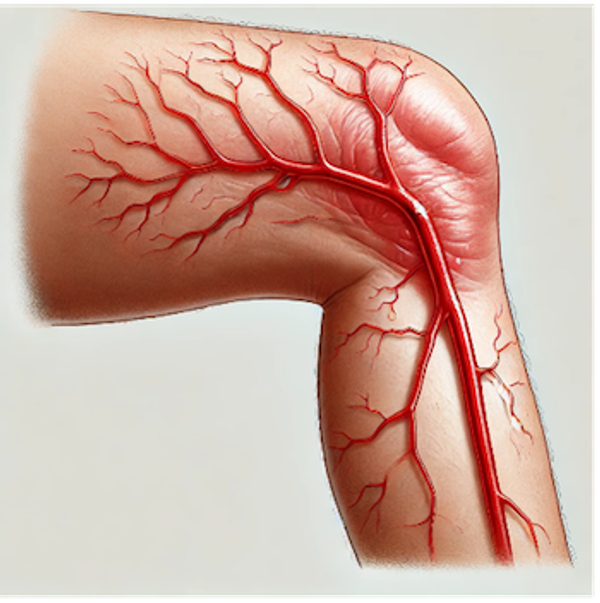

Leestijd: 5 minutenEen aderontsteking is een ontsteking van een oppervlakkig gelegen bloedvat, het wordt ook wel flebitis genoemd. Deze naam komt uit het Grieks van phleps dat ader betekent en itis dat staat voor ontsteking. Als een bloedstolsel en een ontsteking in een ader samengaan, dan wordt dit tromboflebitis of oppervlakkige veneuze trombose genoemd. In deze blog worden beide aandoeningen besproken.

Als een bloedstolsel de oorzaak is van de aderontsteking, dan spreekt men van tromboflebitis oftewel van een oppervlakkige veneuze trombose. Deze vorm van aderontsteking is meestal zichtbaar als een dikke streng. Vaak van enkele centimeters, maar soms ook van langer. Tromboflebitis ontstaat door de vorming van een bloedstolsel in een oppervlakkig bloedvat, waarmee ons afweersysteem aan de gang gaat om dit op te ruimen. Dit veroorzaakt over het algemeen een ontstekingsreactie.

De oorzaak kan langdurige bedlegerigheid zijn, maar soms ook het gebruik van de anticonceptiepil of een zwangerschap. Vaker echter ontstaat het stolsel in een al aanwezige spatader. In een spatader – een verwijde ader – stroomt het bloed niet zo heel erg goed door. De klepjes die normaal in een ader voorkomen dat bloed kan terugstromen, zijn over het algemeen kapot en sluiten niet meer. Hierdoor kan het bloed niet goed meer richting het hart worden teruggepompt. Stolsels kunnen dan door te langzaam stromend of zelfs stilstaand bloed, gemakkelijk ontstaan.

Soms gaat een oppervlakkige trombose over op een dieper gelegen bloedvat, waarna een diep veneuze trombose ontstaat. Dit vindt over het algemeen plaats in de benen en wordt dan ook een trombosebeen genoemd.